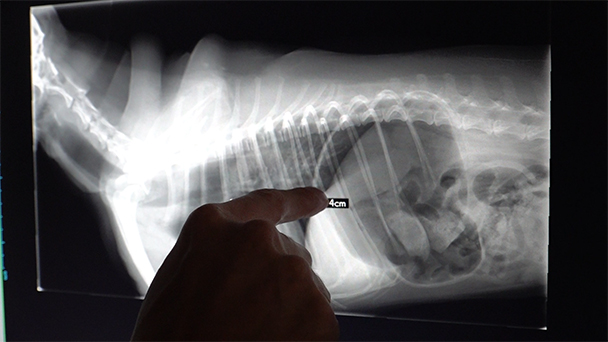

【コーナー③:命の最前線:ネコいぬ救急センター24時】

町の動物病院ではなかなか手がつけられない急な事故や病気、ネコいぬたちの命を救う都内の救急センターに密着。

食道にリンゴを詰まらせ窒息の危機に瀕したいぬの緊急内視鏡手術や、大あくびでアゴが外れてしまったネコを「テコの原理」で救う驚きの処置など、一分一秒を争う現場のリアルを追います。また、15歳の高齢犬の治療を巡り、「何が最善なのか」と葛藤する家族と、その想いに寄り添う獣医師たちの姿。命の尊さと、家族の絆を深く見つめます。